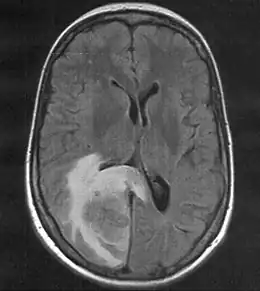

Métastase sur le pôle occipital droit (ici à gauche). La corne dorsale du ventricule latéral est compressé, la ligne médiane est légèrement déplacée.